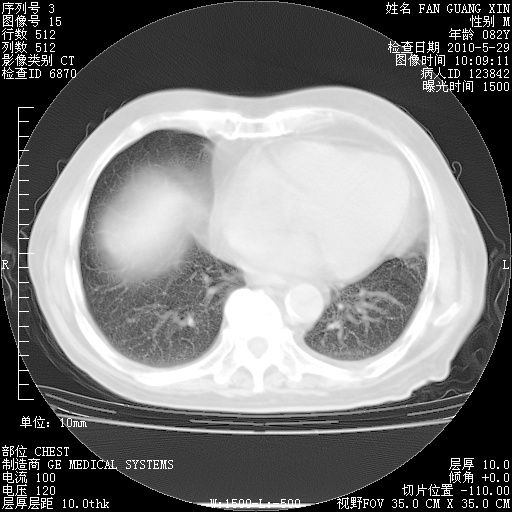

再治疗10天后的肺部CT

阅读此次胸部CT,肺间质渗出性改变较入院时有吸收。目前从体温、白细胞、中性分叶明显增高,肯定存在细菌感染(发生医院感染哦,若无消化道及泌尿系统等感染的依据,肺部感染可能大)。若你院头孢哌酮舒巴坦钠耐药率较高,同意你的方案,若48小时体温仍高,可考虑使用碳青霉稀类抗菌药物,同时可予超声雾化、注意滴数时加大液体量。白蛋白33.30g/L较低哦,需加强营养等支持治疗。